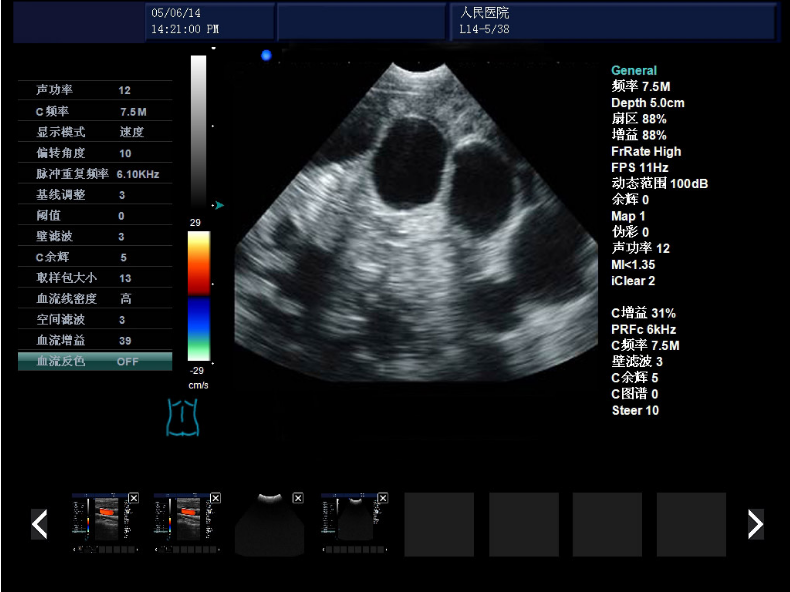

显示模式:B模式(B、B+B、4B、B+M、M)、C模式、D模式、PW模式

发射频率: 具有2.0MHz、3.0MHz、3.5MHz、4.0MHz、5.5MHz、5.0MHz、6.5MHz、9.0MHz、10MHZ、6.0MHz、7.5MHz、12.0MHz变频接收;

动态范围:0-160dB

帧频:9-508fps

脉冲重复频率(PRF):13级可调